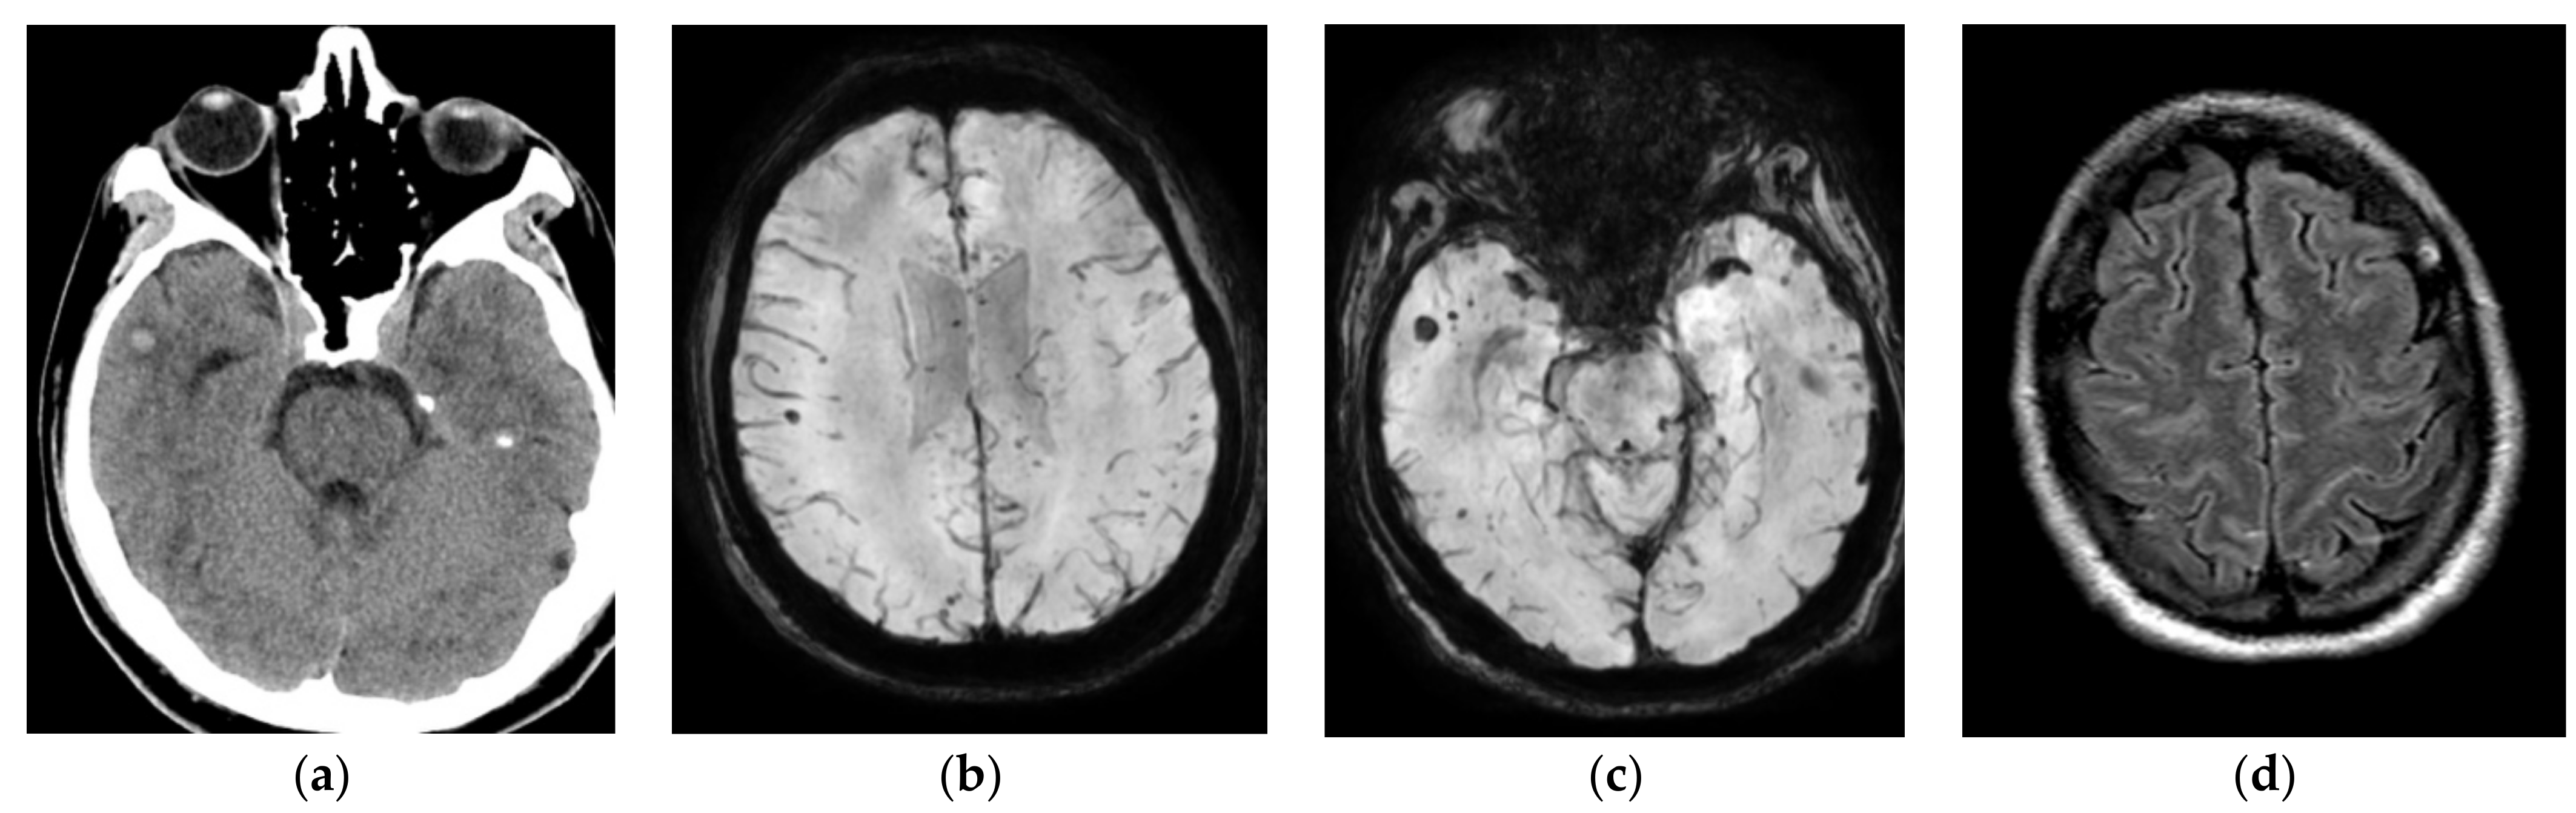

Figure 1. Hemorrhagic lesion in the left temporal lobe and parahippocampal gyrus. The lesion is hyper-intense on the FLAIR axial image (a). The lesion shows mild enhancement on the post-contrast T1 axial image (b). It shows a blooming artifact on susceptibility-weighted imaging (SWI) (c) image. The lesion shows restricted diffusion on the diffusion b 1000 (d).

MRI brain images with and without contrast were obtained in light of the new-onset seizures and temporal hypodensity on CT, which showed intense focal edema within the left hippocampus with mild restricted diffusion, postcontrast enhancement, and hemorrhage seen on susceptibility-weighted imaging (Figure 1). MRA head and neck images did not show any large vessel occlusion or flow-limiting stenosis. The patient was started on empiric cefepime and vancomycin for concerns of meningoencephalitis given the MRI results, and extensive infectious workup was done to assess for the underlying infectious agent. Cerebrospinal fluid (CSF) studies revealed a leucocyte count of 57/μL with neutrophilic predominance (neutrophils: 50%, lymphocytes: 28%, monocytes: 22%), protein of 44 mg/dL, and glucose 59 mg/dL. The CSF gram stain, bacterial culture, and meningitis/encephalitis panel (including cytomegalovirus, enterovirus, E. coli K1, Hemophilus influenzae, herpessSimplex virus (HSV)-1, and HSV 2, human herpes virus 6, Listeria, Neisseria meningitidis, parechovirus, Streptococcus agalactiae, Streptococcus pneumoniae) were negative. Varicella zoster virus (VZV) PCR, cryptococcal antigen, culture, acid fast bacilli (AFB) smear and culture, and Cytomegalovirus (CMV) PCR were negative. CSF VZV IgG were found to be greater than 4000 IU. Infectious disease (ID) was consulted and vancomycin and cefepime were continued for a total of 14 days as per their recommendation for concern of encephalitis due to neutrophilic pleocytosis in CSF. The patient’s clinical course was stable during the course of admission. He did not have any further seizure episodes. He was discharged home on the tenth day of admission. He continued to have occasional headaches after discharge but otherwise was completely back to baseline. An MRI brain scan done 7 weeks later showed a persistent susceptibility artifact, suggestive of hemorrhage in the left parahippocampal gyrus with a resolution of adjacent enhancement and mass effect with interval volume loss. Overall, he manifested self-limiting hemorrhagic encephalitis in the setting of mild systemic COVID-19 disease.

On day 26, the patient became more encephalopathic, became non-verbal, and had an episode of rapid eye fluttering and gaze deviation, and neurology was consulted for concerns of stroke/seizures. Upon examination, the patient was diaphoretic, opening eyes spontaneously, mute but following simple commands, and moving all four extremities spontaneously. A stat CT head and CT angiogram head and neck were obtained for concerns of acute stroke which showed a small right temporal hyperdensity (0.6 cm diameter) suggestive of a hemorrhage with normal vasculature (Figure 2). The patient was started on Levetiracetam and transferred to ICU for closer monitoring. An MRI of the brain with and without was obtained in light of the acute hemorrhage which showed a stable small right anterior temporal lobe intraparenchymal hemorrhage, additional multiple scattered foci of susceptibility artifact, particularly in the gray–white junctions and corpus callosum, and sulcal FLAIR hyperintensity in the right frontal, biparietal, and left temporal lobes without any postcontrast enhancement (Figure 2). The patient was started on VEEG for 24 h for new-onset status epilepticus which showed generalized slowing without any ictal or inter-ictal discharges. CSF studies showed glucose of 28 mg/dL, protein of 118 mg/dL, xanthochromia with 91,000/μL RBCs, 270/μL WBCs with neutrophilic predominance (80%). Other CSF studies including Meningitis/encephalitis panel, AFB smear and culture, cryptococcal antigen, and VZV PCR, CMV PCR, CSF cytology were negative. The patient’s mental status improved with levetiracetam and he was transferred to the floor on day 29. His mental status continued to improve to the point that he returned back to his normal self and was discharged on day 32 with levetiracetam for 2 weeks. He was seen in the clinic after 1 month and did not have any seizures but complained of recurrent headaches. His exam was unremarkable.